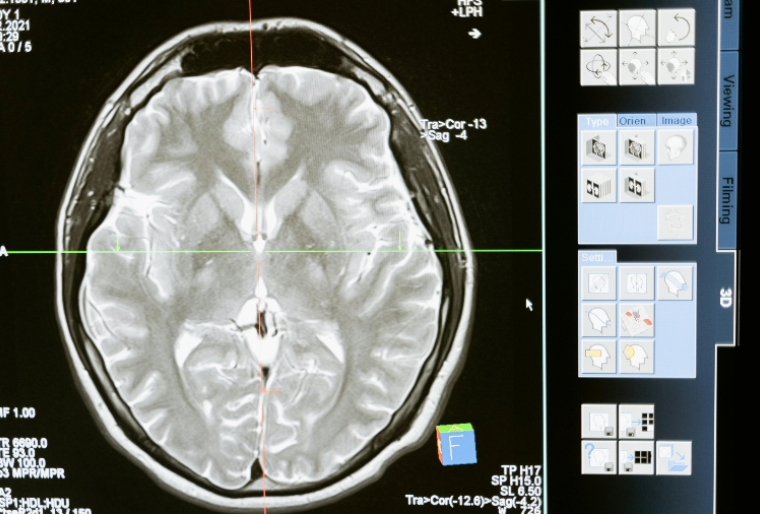

O diagnóstico da EM exige uma investigação cuidadosa, pois não há um exame único e definitivo. O neurologista avalia o histórico clínico, sintomas e realiza exames como a ressonância magnética, que detecta lesões no cérebro e medula espinhal. Em alguns casos, o médico também solicita uma punção lombar para analisar o líquido cefalorraquidiano.